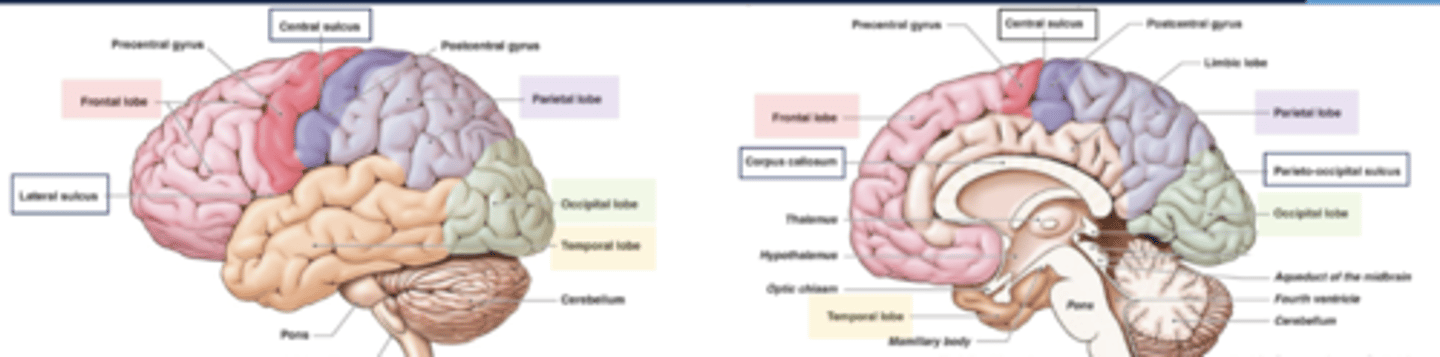

list the functions of the frontal lobe:

1. movement

2. executive functions

3. problem solving

4. reasoning/judgement

5. behaviors (emotions)

6. language production

7. memory

list the functions of the parietal lobe:

1. sensation

2. body orientation

3. spatial relationships

~primary somatosensory cortex~

list the functions of the temporal lobe:

1. language comprehension

2. hearing

3. behavior

4. memory

list the functions of the occipital lobe:

1. vision

2. color perception

list the functions of the cerebellum:

1. balance

2. coordination

3. fine muscle control

list the functions of the brainstem:

1. breathing

2. blood pressure

3. heartbeat

4. swallowing

5. alertness/sleep

6. body temperature

7. digestion

what are the boundaries of the frontal lobe?

central sulcus and lateral fissue

what are the boundaries of the parietal lobe?

central sulcus, lateral fissure, parieto-occipital sulcus

what are the boundaries of the occipital lobe?

parietal-occipital sulcus

what are the boundaries of the temporal lobe?

lateral fissure